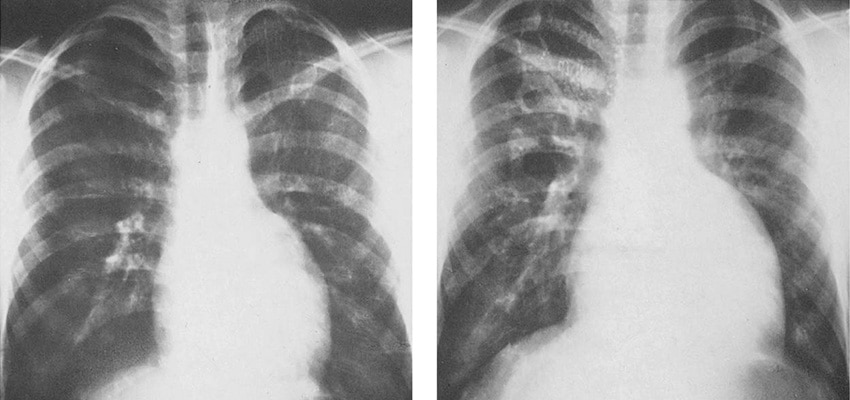

سی تی اسکن قلب یکی از روش های تشخیصی دقیق و آسان بیماری سرخرگهای کرونر قلب (CAD)، آزمایشهای پزشکی هسته ای می باشند که مهمترین و متداول ترین نوع آنها تصویربرداری (اسکن) پرفیوژن میوکارد است.

در سی تی اسکن قلب از یک ماده رادیو اکتیو بی خطر ، خون رسانی به عضله قلب در دو حالت ورزش و استراحت بطور جداگانه مورد بررسی دقیق قرار می گیرد.

پس برای بررسی دقیق تر وضعیت خون رسانی به عضله قلب بهتر است قلب را در شرایط فشار بررسی کنیم تا آن منطقه که دچار افت نسبی جریان خون (ایسکمی) به علت تنگی سرخرگی است با اسکن قلب خود را بهتر نشان دهد .

در این صورت با تشخیص منطقه مبتلا به افت جریان خون ، با سی تی اسکن قلب بطور غیر مستقیم سرخرگ مبتلا به تنگی را شناسایی کرده و با درمان بموقع تنگی ، از پیشرفت بیماری و خطرات بعدی پیشگیری خواهد شد. بنابراین اسکن قلب باید با آزمون ورزش انجام شود. آزمون ورزش که حداکثر نیم ساعت بطول می انجامد یا با دوچرخه و یا با دستگاه تردمیل ( Treadmill) انجام میشود.